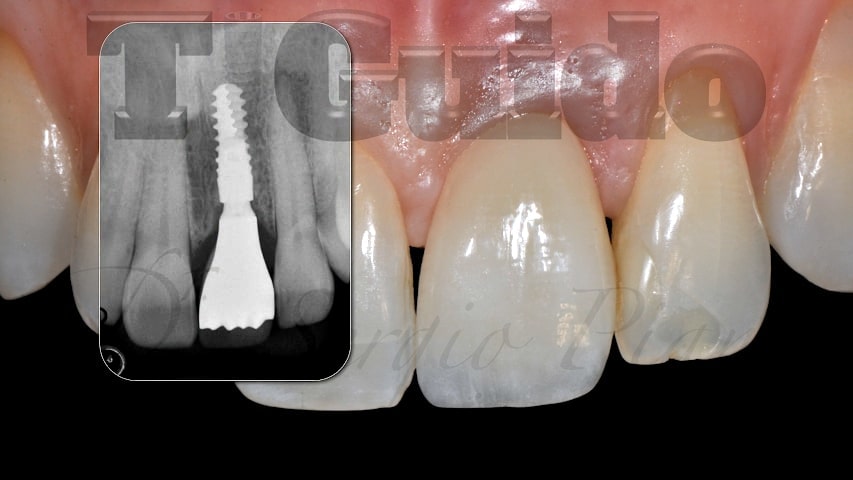

Alcuni nostri casi